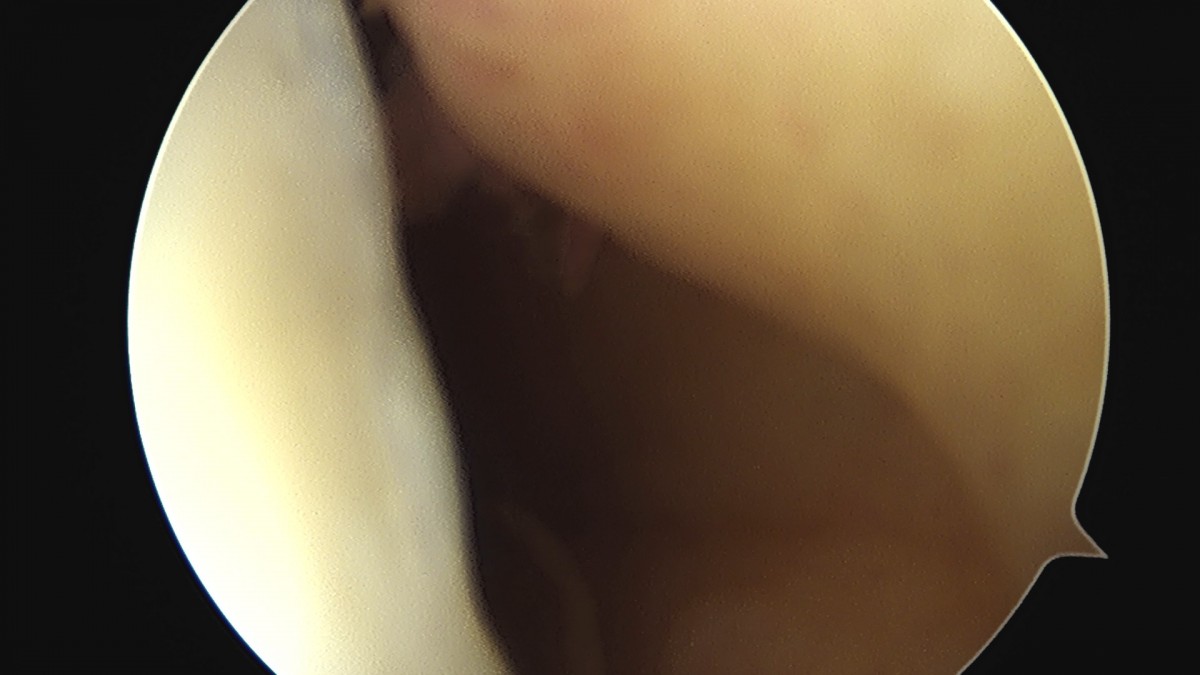

이재상원장님 무릎 전방십자인대 재건술 및 반월상 연골판 절제술 유해O 환자

dae765e4d9ac96aee867c9d6292d8784_1758007656_3563.jpg